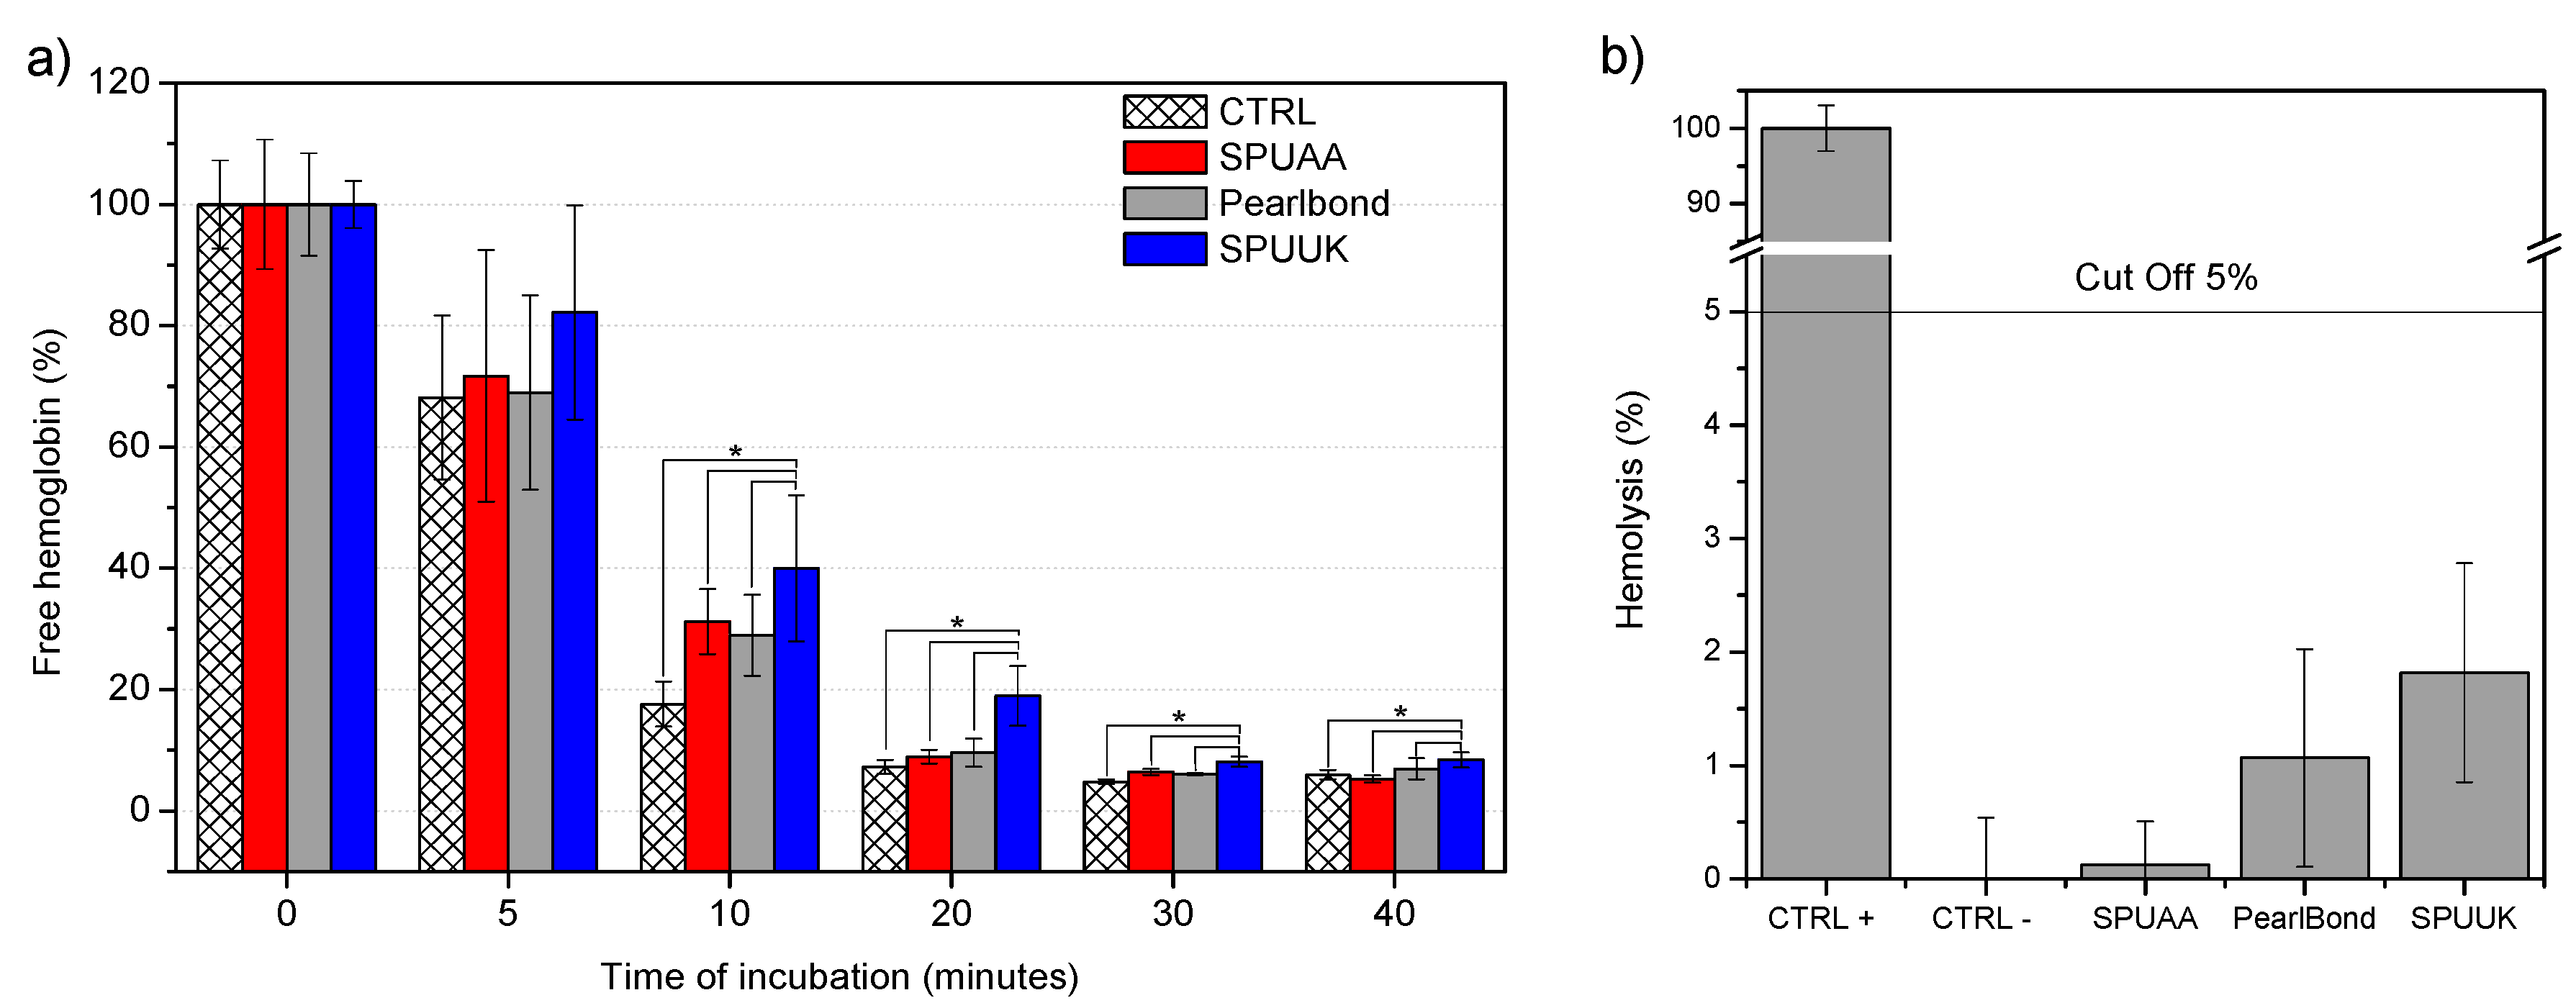

2.8.3. Clot Formation

2.8.4. Hemolysis

3.5.3. Hemocompatibility